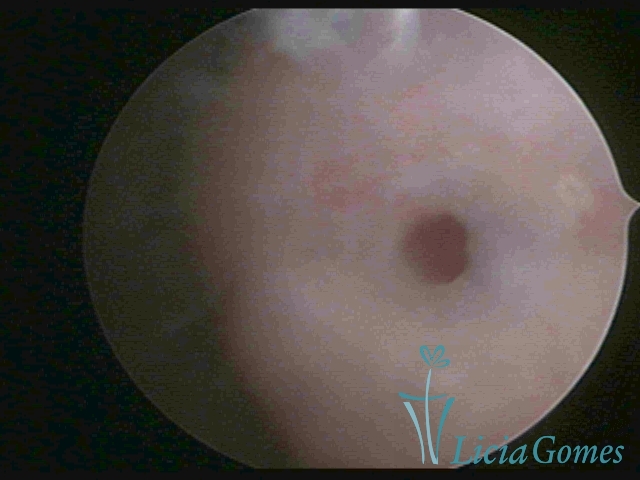

Terceira porção ou porção superior

Apresenta a mucosa com a superfície lisa e pouco vascularizada até a altura do orifício interno